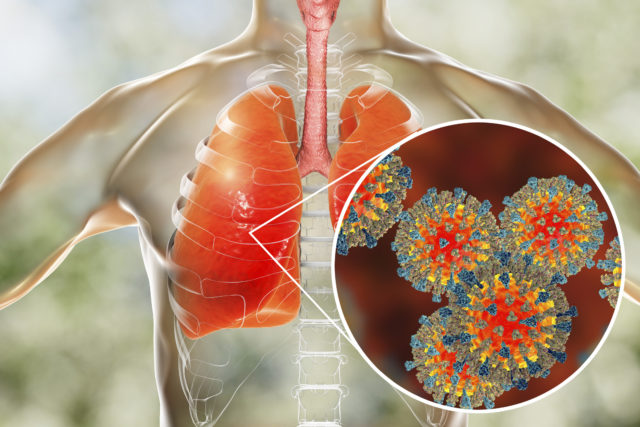

Podľa britského denníka Daily Mail dánski zdravotníci tvrdia, že výskyt mykoplazmovej pneumónie, bakteriálna infekcia, ktorá nereaguje na antibiotiká, dosiahol „epidemickú“ úroveň. Peking naznačuje, že rovnaký patogén je čiastočne zodpovedný za „záhadnú“ vlnu detských zápalov pľúc, ktoré sa vyznačujú nebezpečným zápalom pľúc.

Šírenie nakazených osôb vyvolalo obavy, že sa nákaza môže šíriť aj v Európe. Mycoplasma pneumoniae sa zvyčajne prejavuje miernymi príznakmi podobnými chrípke a nakazení jedinci trpia horúčkou, únavou, bolesťami hlavy, krku a dlhotrvajúcim kašľom. Väčšina prípadov sa vyskytuje u detí vo veku 6-12 rokov.

Odborníci označujú toto ochorenie ako „atypický zápal pľúc“. Je to preto, že penicilín, bežné antibiotikum, ktorým sa obvykle liečia bakteriálne infekcie, nezaberá. Podľa Hanne-Dorthe Emborgovej, vedúcej výskumnej pracovníčky SSI, však táto epidémia nie je ničím neobvyklým a odborníci ju predpovedajú už dlhšiu dobu.

‚Mycoplasma pneumoniae‘

Atypické pneumónie sú pneumónie spôsobené inými organizmami ako tzv. typické baktérie, vírusy alebo plesne. Najčastejšími príčinami sú mykoplazmy a chlamýdie – dva organizmy podobné baktériám.

Zápal pľúc spôsobený mykoplazmou zvyčajne začína únavou, bolesťou v krku a suchým kašľom. Príznaky sa postupne zhoršujú. Silné záchvaty kašľa môžu produkovať hlien. U niektorých ľudí sa tiež objaví vyrážka. Niekedy sa objavia anémia, bolesti kĺbov alebo neurologické problémy. Príznaky zvyčajne trvajú jeden alebo dva týždne a potom sa pomaly zlepšujú. Niektorí ľudia sa môžu aj po niekoľkých týždňoch cítiť slabí a unavení.

Mykoplazmový zápal pľúc môže mať závažný priebeh, ale zvyčajne je mierny a väčšina ľudí sa uzdraví bez liečby. Atypický zápal pľúc je tiež spôsobený baktériou Mycoplasma pneumoniae. Mykoplazma zvyčajne spôsobuje mierny zápal pľúc a epidémie sa objavujú raz za 4-6 rokov. Epidémie sa obvykle objavujú na jeseň a postupne prebiehajú niekoľko mesiacov, niekedy trvajú až do jari.

Nárast počtu zápalov pľúc v krajine bol nazvaný „syndróm bielych pľúc“ kvôli spôsobu, akým sa poškodenie pľúc prejavuje na snímkach u detí.